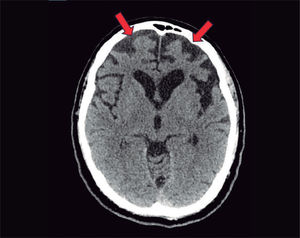

En la resonancia magnética, se visualiza una atrofia de las sustancias gris y blanca frontotemporal.